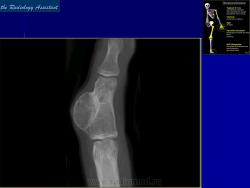

Периостальная хондрома

Периостальная хондрома (син.: юкстакортикальная хондрома, паростальная хондрома редкая доброкачественная опухоль, состоящая из зрелой хрящевой ткани и расположенная над надкостницей. Обычно она разрушает наружную часть коркового слоя, но не прорастает в костно-мозговой канал. Мужчины болеют в два раза чаще женщин. Типичная локализация — проксимальный конец плечевой и бедренной кости дистальный конец бедренной кости, а также фаланги. В редких случаях одновременно поражается несколько костей. Периостальная хондрома обнаруживается большей частью в метафизарной части, лишь у 30 % больных поражаются диафизы. Опухоль достигает в среднем 2—3 см в диаметре. Она окружена зоной остеосклероза и сопровождается периостальным остеогенезом, так что на границе опухоли с костью образуется грушевидное углубление с четкими контурами. Под микроскопом периостальная хондрома имеет тонкие контуры, она как бы погружена в корковый слой и покрыта надкостницей, как тонкой скорлупой. На разрезе ее ткань синюшно-серая или белая, хрящевые элементы обладают дольчатым строением. Участки обызвествления имеют вид желтовато-белых вкраплений. Эта опухоль состоит из гиалинового хряща, дольки которого разделены фиброзными прослойками или костными балками, местами обызвествленными. Кое-где отмечается проникновение опухолевых клеток в костномозговой канал, на большем же протяжении внутренний контур образован компактной костью.

Дифференциальная диагностика представляет известные трудности в тех случаях, когда периостальная хондрома имеет сходство с юкстакортикальной хондросаркомой.